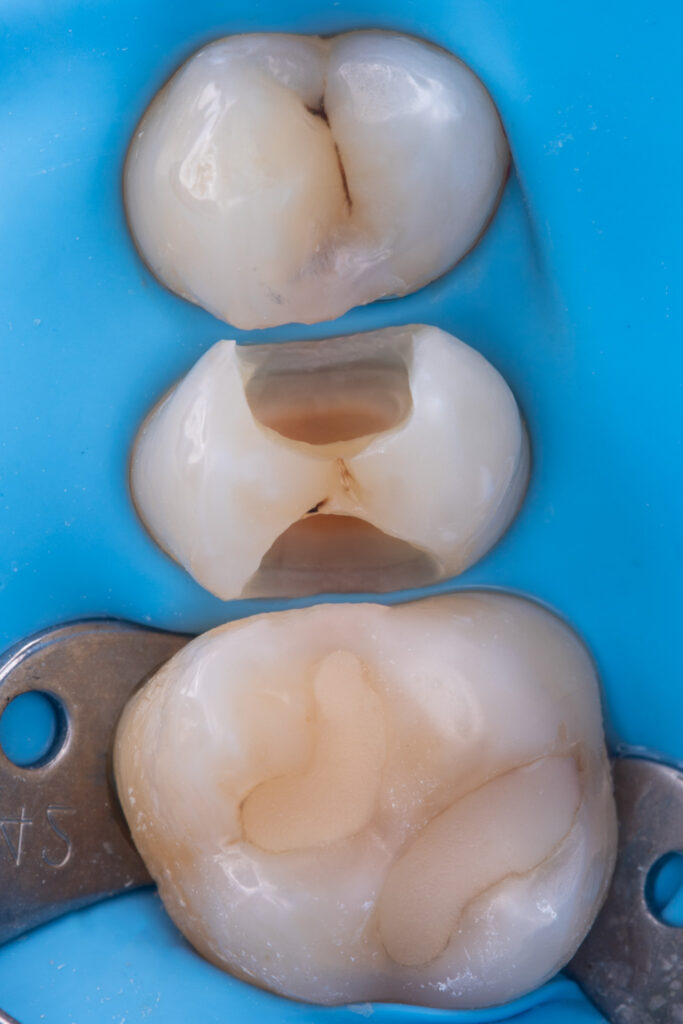

For restoration of the proximal walls, Asteria A3B composite resin was used.

EvoCeram Dentin 2 was applied as the dentin substitute.

Final anatomical contouring of the tooth was performed using NeoSpectrum A2 composite resin.

The total treatment time was 1 hour and 15 minutes.